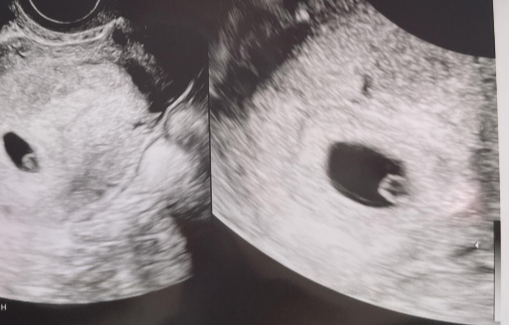

하루 이틀 지날수록 테스트기는 점점 진해졌고 12월 31일 날 병원에 방문해서

아기집을 확인했다.